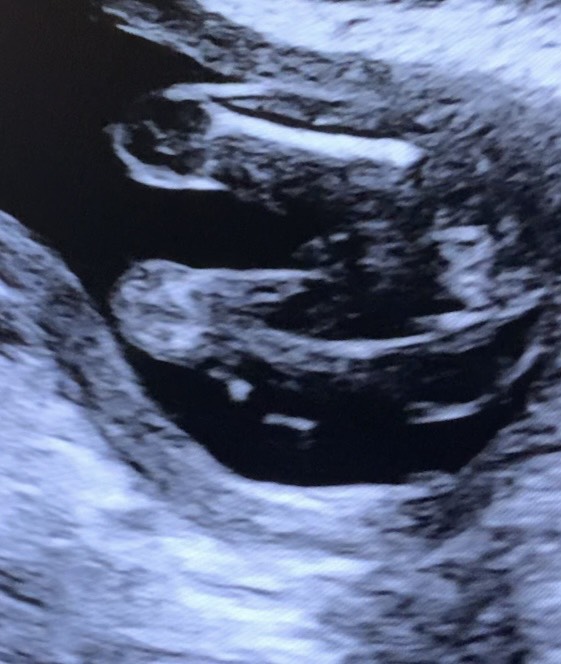

Кого вы видите на первом фото? А на втором?😅

Срок на узи ровно 19 недель (по первому скринингу) разница в фото несколько секунд

На первом фото видно половые губы , на втором видно мальчика 🤣

Очертания писюна и мошонки на обоих )